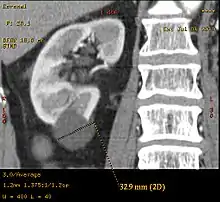

| Renal cyst of the left kidney (hyperintense area) as shown on MRI. | |